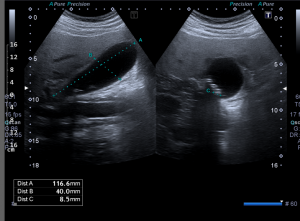

Vyšetření provádí erudovaný lékař, který pro danou vyšetřovanou oblast zvolí vhodnou ultrazvukovou sondu a nastaví optimální parametry přístroje. Pacient při vyšetření leží na vyšetřovacím stole a dodržuje pokyny lékaře. Nejčastěji se vyšetření provádí vleže na zádech, na břiše nebo na boku. Kůže pacienta se ve vyšetřované oblasti pokrývá vrstvou gelu pro sonografii. Lékař plynule pohybuje po pacientově těle ve vyšetřované oblasti ultrazvukovou sondou a při tom sleduje obraz na monitoru. Vyšetření se provádí v různých rovinách daných postavením sondy, někdy i v různých polohách pacienta. Během vyšetření lékař v případě potřeby provádí různá měření. Při vyšetření asistuje vyškolená sestra, která pomáhá především s odstrojením a uložením pacienta, provádí administrativní úkony a řídí objednávání pacientů. Před vyšetřením sestra nebo lékař vysvětlí pacientovi stručně, jak vyšetření probíhá a co je jeho cílem, eventuelně rozptýlí případné obavy pacienta z vyšetření. Na závěr vyšetření pak lékař pacientovi co nejsrozumitelněji vysvětlí zjištěný nález, jeho závažnost a případné další důsledky. Obrazová dokumentace je zhotovena tiskem na speciální papír, eventuelně je provedena digitální archivace obrazu.

Na našem pracovišti provádí lékaři radiodiagnostického oddělení ultrazvukové vyšetření břicha, třísel, axil, krku a povrchových rezistencí.